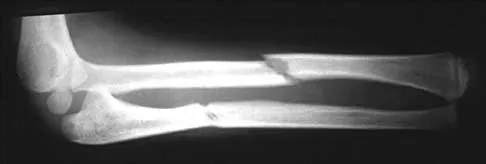

Figure 43 shows the lateral radiograph of a 12-year-old boy with mild osteogenesis imperfecta who injured his left elbow after pushing his brother. Treatment should consist of

Figure 31 shows the radiograph of an 8-year-old boy who has a swollen forearm after falling out of a tree. Examination reveals that all three nerves are functionally intact, and there is no evidence of circulatory embarrassment. Management should consist of